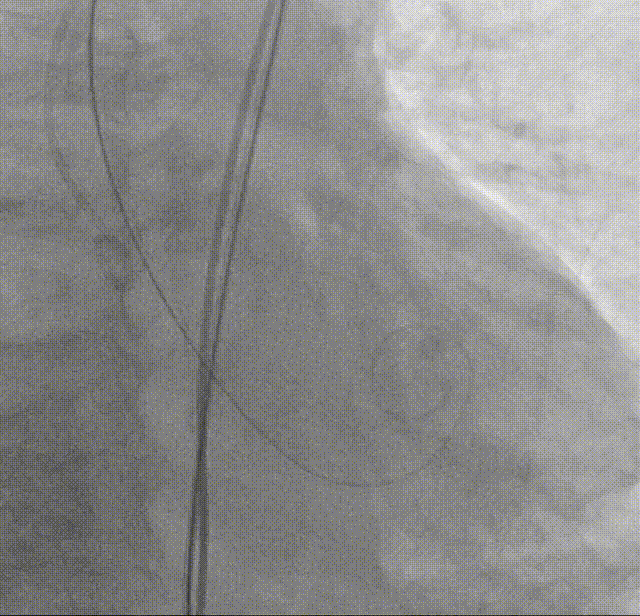

AL1导管+直头导丝顺利跨瓣

导管测压:跨瓣压差高达120mmHg

18mm球囊预扩:可见无腰有漏,经评估决定装载TAVTF25瓣膜